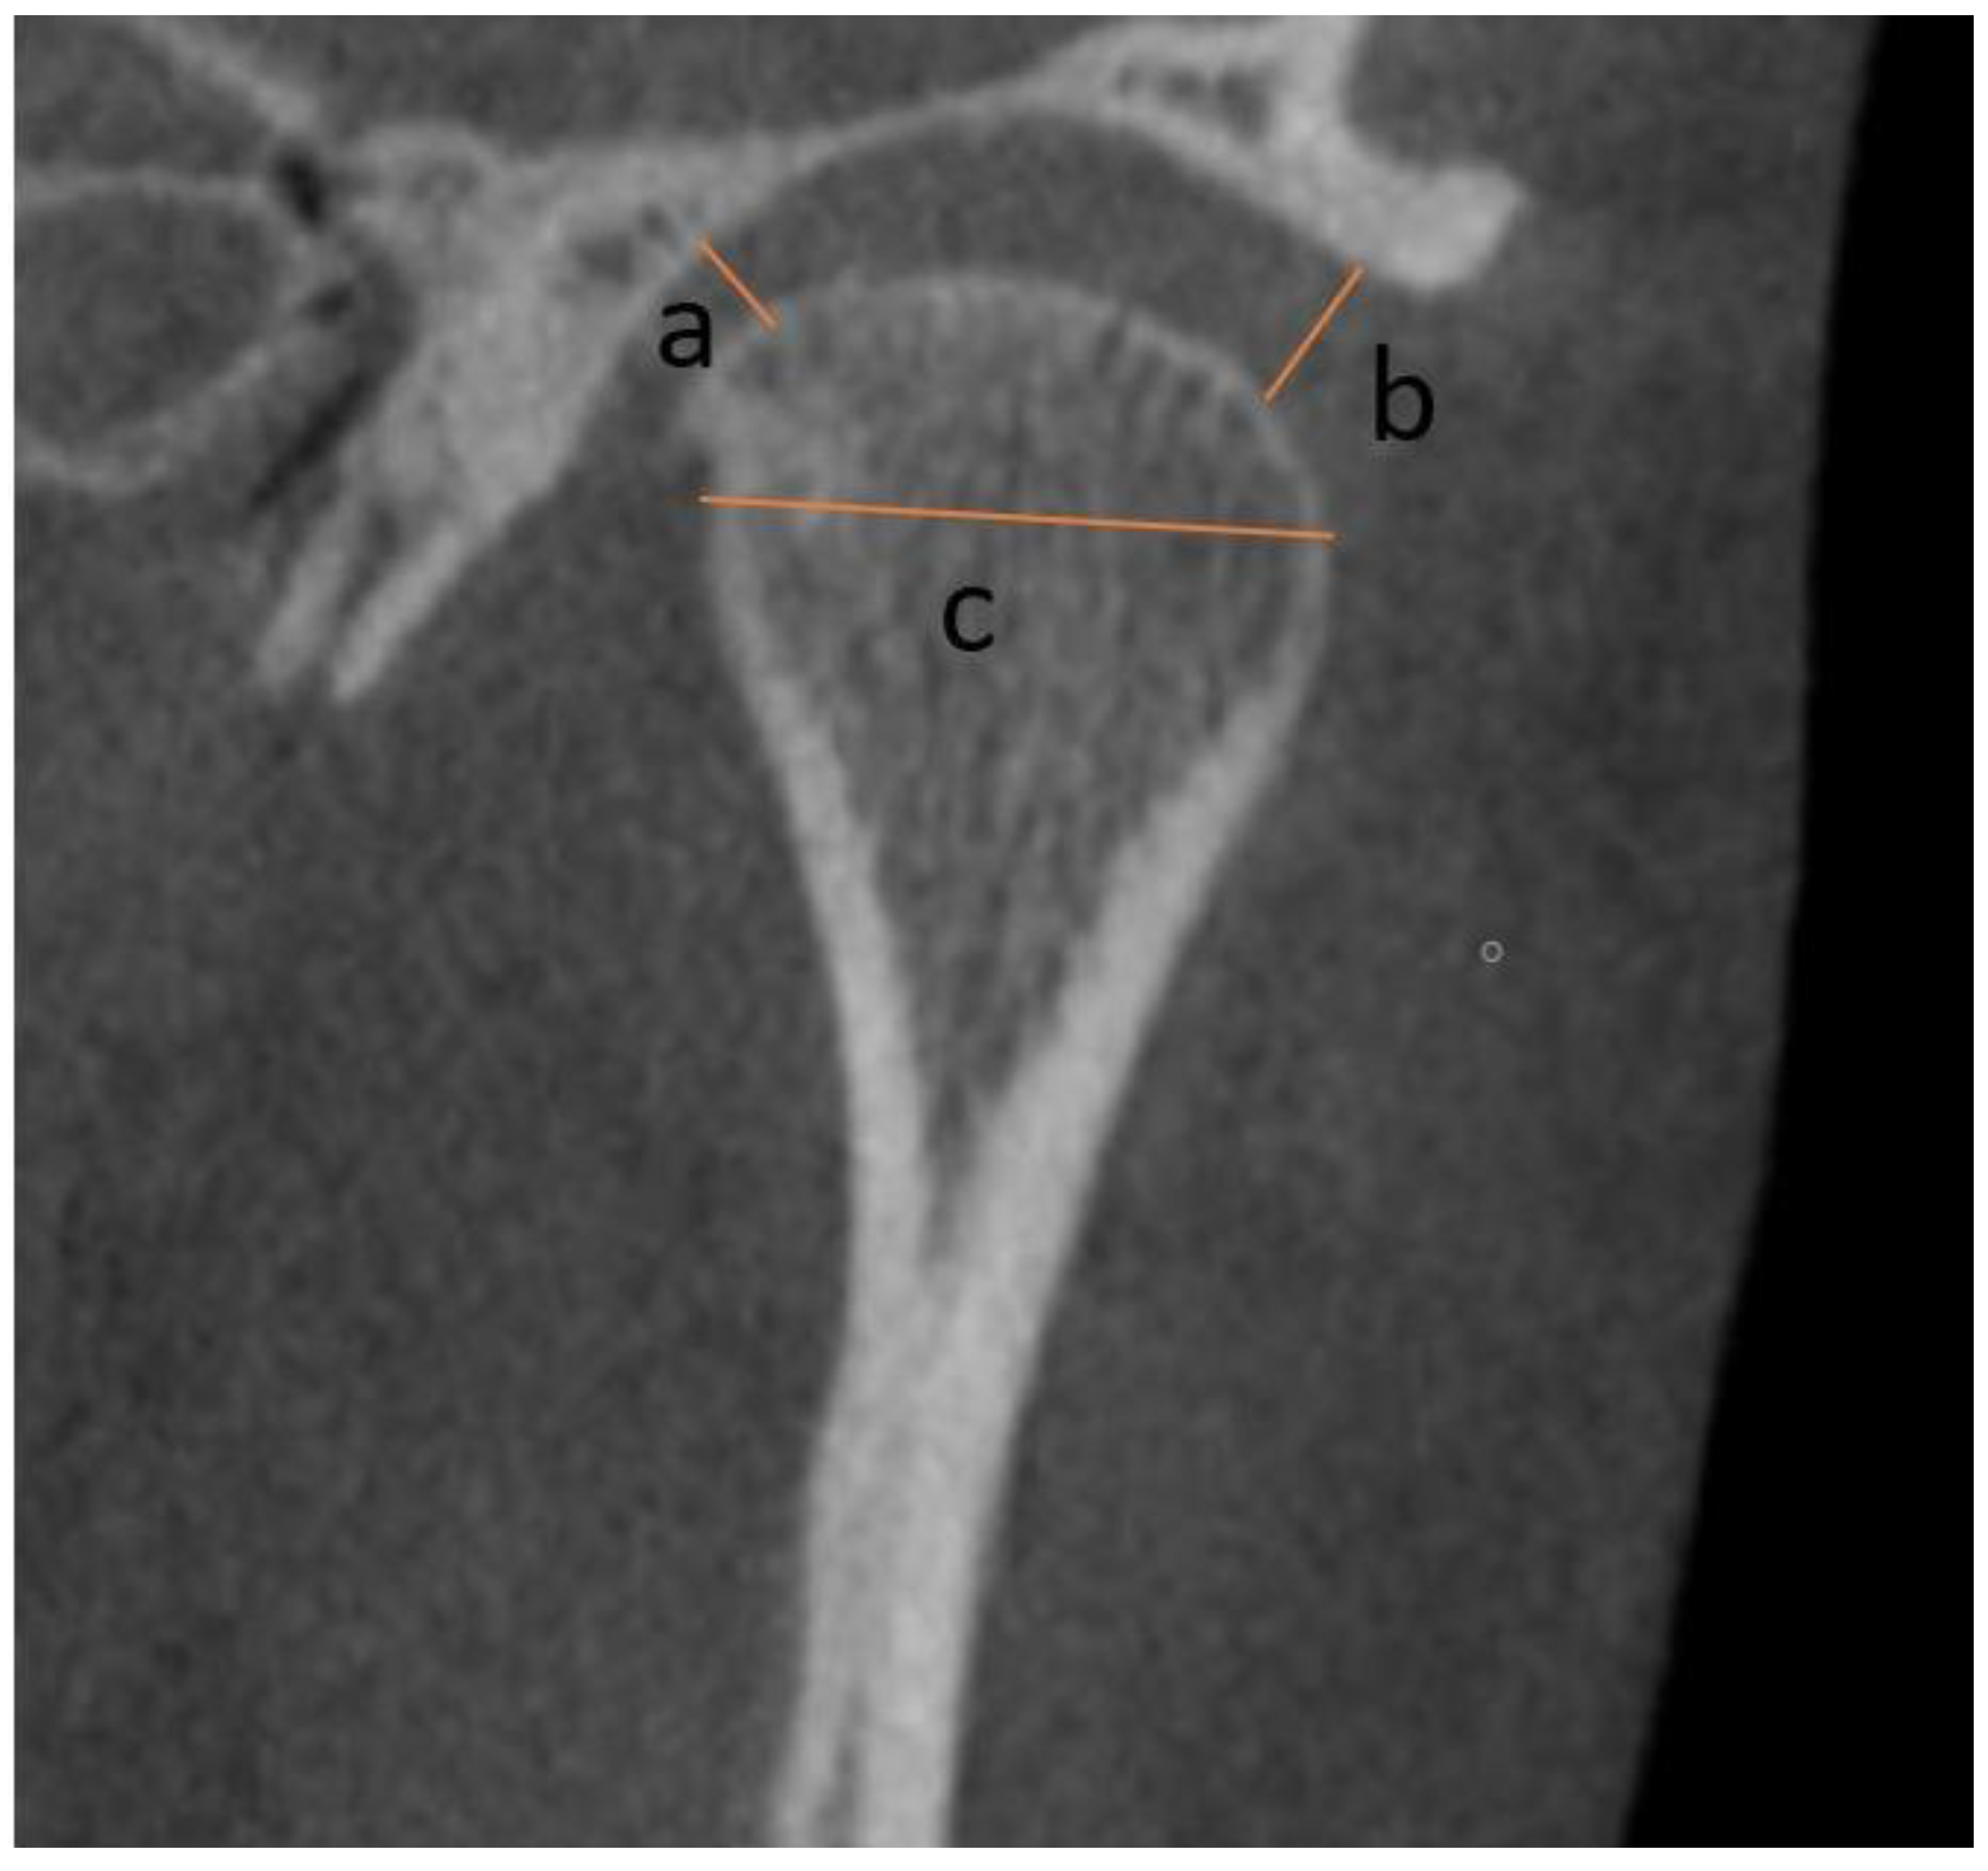

2.2. Measurements